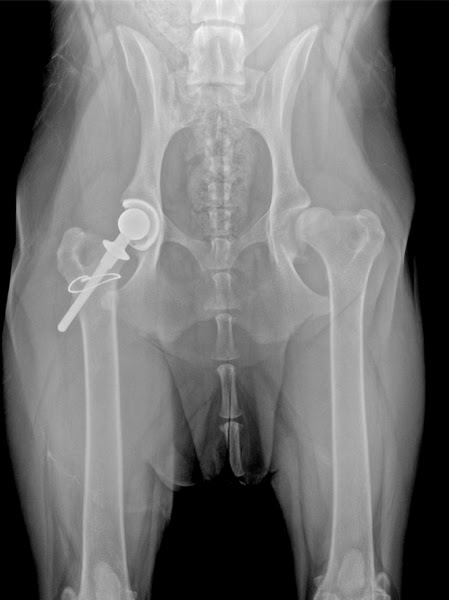

The age of the dog older dogs require special care and the surgery involves more risks The breed The overall health condition of the pet The type of materials used titanium is more expensive than. Radiograph x-ray showing arthritis in a dog that would benefit from Canine Total Hip Replacement. Who performs the surgery.